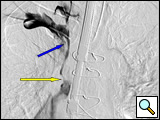

General anesthesia is utilized. Due to the patient's upper airway swelling from SVCS, airway access may be difficult, often necessitating the use of fiberoptic intubation. The patient is positioned supine with both arms placed at 90 degrees. Both arms are prepped in as well as both groins for access. Large bore IV access may be a problem secondary to the extensive upper extremity venous collaterals. Use of the SonoSite Ultrasound® (SonoSite Inc. Bothell, WA) for deep venous access of the upper extremities may be warranted. Two short 6F sheaths placed in the right and left cephalic veins (or one placed in the upper extremity and one in the groin via the common femoral vein) are necessary for access. A soft angled Glide catheter is necessary to access the great veins of the upper mediastinum down to the superior vena cava, and a soft angled Glide catheter placed into the SVC is necessary for performing the contrast venogram of the upper extremities and SVC to localize and define the extent of clot (Figures 2A and 2B).

Figure 2A: AP venogram of left subclavian vein from the right groin catheter demonstrating extensive intravascular clot at the arrow and catheter tips.

Figure 2B: Selective venogram of the right subclavian vein taken from the right brachial catheter visualizing the SVC junction with a small venous "trickle" (yellow arrow) draining into the SVC. There is extensive thrombus just at the tip of the infusion catheter and blue arrow.